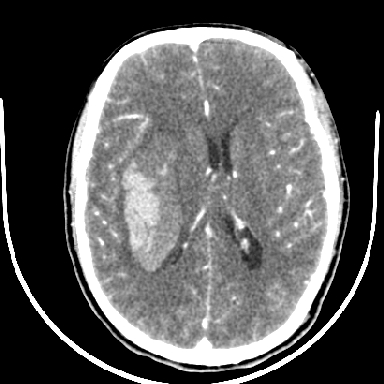

标题: CT6056:脑出血(血管畸形?) [打印本页]

标题: CT6056:脑出血(血管畸形?)

m 40突发头痛左侧偏瘫3小时

考虑高血压性脑出血,依据:

1是高血压性脑出血的好发部位,形态呈肾形,是高血压性脑出血的常见形状

2增强时占位效应加重了,考虑出血还没有停止

3病灶周围水肿不是太厉害,一般肿瘤出血水肿多非常明显

4病灶周围的‘软组织’影没有明显的强化

5至于脑血管畸形引起的出血,暂时没有看到明显的畸形血管影,也不太支持

支持右侧基底节脑出血

右侧基底节区脑出血.

支持右侧基底节区(主要为外囊区)原发性脑出血。

另附部分资料:“血液溢出血管外形成血肿,其内含有大量血红蛋白、血浆白蛋白,球蛋白,因这些蛋白对x线的吸收系数高于脑质,故ct呈现高密度阴影,ct值达40~90h,最初高密度灶呈非均匀一致性,中心密度更高,新鲜出血灶边缘不清。基底节区血肿多为“肾”型,内侧凹陷,外侧膨隆,因外侧裂阻力较小,故向外凸,其它部位血肿多呈尖圆形或不规则形”

术中抽出40ml陈旧血液,血肿底部似见一条索血管影